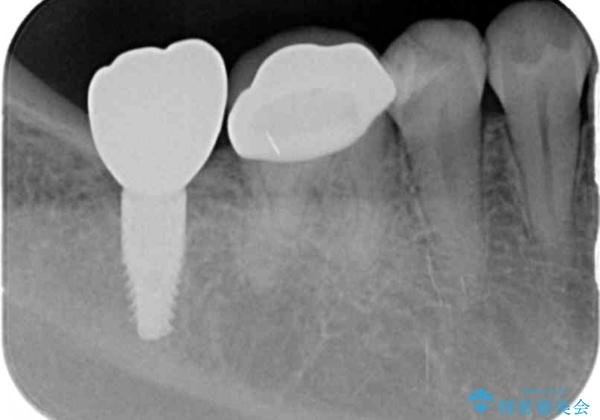

奥歯のインプラント治療

- 右下の奥歯を虫歯で喪失しそれ以来よく物が噛めず、改善を求めて来院されました。

入れ歯かインプラント治療のご提案を行い、よりしっかりとかめるインプラント治療を希望されました。

骨との結合する期間が早く、大きな咬合力にもしっかりと耐えることのできるストローマンインプラントを用いた咬合機能回復を計画します。

- 44万円(ストローマンインプラント・チタンカスタムアバットメント・仮歯・フルジルコニアクラウン)費用は治療当時の料金となります